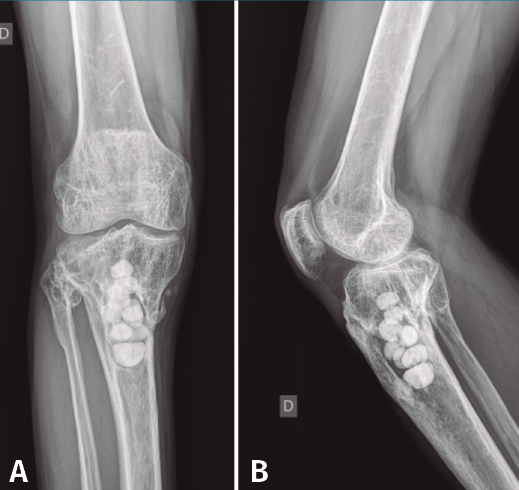

Figura 5. Radiografías de frente y de perfil del extremo proximal de la tibia donde se objetiva la cavidad en la tibia con presencia de material granulado en su interior.

En el estudio radiológico (Figura 5) se objetiva imagen cavitaria en el extremo proximal de la tibia con presencia de material granulado del injerto realizado.

Figura 7. Radiografías de frente y de perfil del extremo proximal de la tibia tras el desbridamiento de la cavidad y el relleno con bolas de cemento con antibiótico.

Con el diagnóstico de osteítis crónica de la tibia se realiza desbridamiento óseo de la cavidad y amplia resección ósea de cortical tibial medial, y relleno de la cavidad con bolas de cemento con antibiótico (Figura 7), con posterior tratamiento antibiótico.